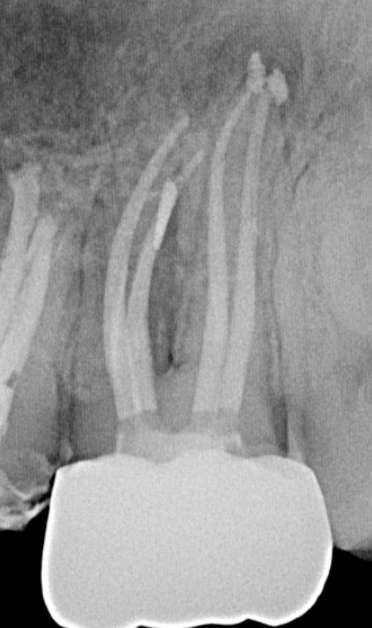

Röntgenologischer Befund: Therapie

Das präoperativ angefertigte diagnostische Röntgenbild zeigt eine insuffiziente Amalgamfüllung im distalen Approximalraum. Die mesiale Wurzel weist eine periapikale Osteolyse auf (Abbildung 1).

Abbildung 1: Präoperative Diagnostische Aufnahme